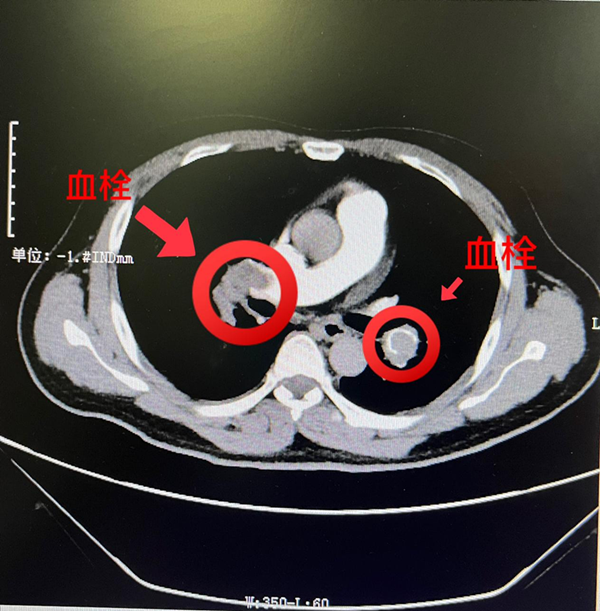

科主任黄小龙根据患者的症状和病史,行胸部CTA检查,明确诊断为“双侧肺动脉主干及其分支栓塞”。患者病情凶险,需要立即进行手术。经过术前团队讨论,并与家属充分沟通,决定为患者进行“肺动脉造影+肺动脉血栓碎栓术+下腔静脉滤器置入术+介入下溶栓术”。术中为患者给予导管溶栓和腔静脉滤网植入术,肺动脉血栓大部分消除,术后造影复查,可见左侧肺动脉血栓明显减少,血管通畅,患者血氧饱和度基本升至正常,呼吸情况明显改善。术后针对患者下肢血栓进行系统治疗,进一步预防肺动脉再次栓塞,术后患者恢复良好,大年二十九康复出院回家过年啦!“能赶在除夕前回家实在是太好了,你们医术精湛,护理暖心,真的太感谢所有医护人员的精心照顾啦!”患者及家属出院前兴奋地表示。

同样因为肺栓塞入院的还有一位55岁的梁女士,新春前因“气促伴呼吸困难5天,晕厥2小时”急诊入住呼吸内科,入院时,患者已经出现血氧饱和度低、心率增快等危急症状。医生对患者进行了肺动脉CTA检查提示该患者双侧肺动脉主干及其分支多发栓塞,患者同时合并病毒性肺炎,经过心胸乳腺血管外科主任黄小龙全面评估患者病情及结合各项检验指标,判断属于中高危型肺栓塞!如果不及时且规范治疗,患者随时可能因呼吸、循环衰竭死亡!